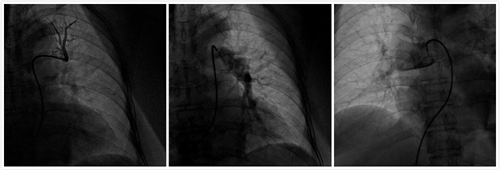

患者,女性,62歲,曾從事油漆工工作,工作有長時間站立、下蹲特點。因活動后胸悶、氣短、呼吸困難3日,加重1日主訴入院,入院后經(jīng)心內(nèi)二科張曉鋒主任、呂強副主任醫(yī)師仔細(xì)分析患者癥狀及心電圖、血氣分析后,肺動脈CTA檢查迅速明確診斷,確定該患者介入手術(shù)適應(yīng)證,預(yù)計會有較好的療效。在充分與患者及家屬溝通,同意肺動脈造影及抽栓、碎栓、藥物溶栓手術(shù)治療。呂強副主任醫(yī)師、張曉鋒主任醫(yī)師、潘立棟醫(yī)師、邵玉玲主管護師、車曉偉技師組成的手術(shù)小組在經(jīng)歷一個多小時緊張而有條不紊的操作后,順利完成了肺動脈血栓抽栓、碎栓、藥物溶栓搶救。患者術(shù)后取得了立竿見影的效果,胸悶、氣短、呼吸困難明顯減輕,次日復(fù)查動脈血氣分析氧分壓明顯改善,目前患者恢復(fù)良好。

△ 溶栓前

△ 溶栓后

該手術(shù)的成功開展,不僅使患者低氧、休克癥狀快速緩解、生命得到救治,為急性肺動脈栓塞合并有休克、循環(huán)衰竭的重癥患者搶救提供了新的方法和思路。同時,也標(biāo)志著西安高新醫(yī)院心內(nèi)科在治療搶救急性肺動脈栓塞的方法取得了創(chuàng)新性的突破,為該項新技術(shù)的進一步開展積累了臨床經(jīng)驗,使醫(yī)院在肺動脈栓塞搶救領(lǐng)域達(dá)到了省內(nèi)較高水平。西安高新醫(yī)院心內(nèi)二科將以此為契機,不斷提高急性肺動脈栓塞的早期確診水平和救治成功率,為更多的此類危重患者帶來福音